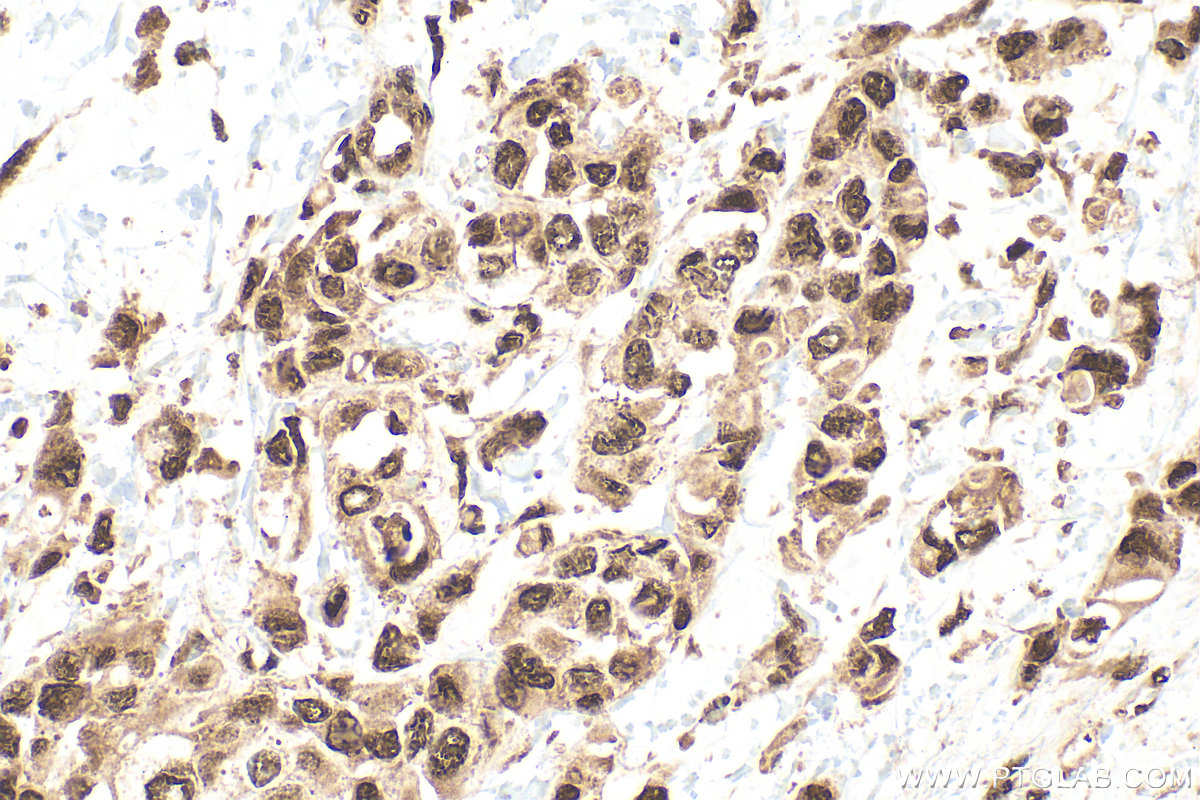

| Positive IHC detected in | mouse brain tissue, human breast cancer tissue, human colon tissue Note: suggested antigen retrieval with TE buffer pH 9.0; (*) Alternatively, antigen retrieval may be performed with citrate buffer pH 6.0 |

| Immunohistochemistry (IHC) | IHC : 1:50-1:500 |